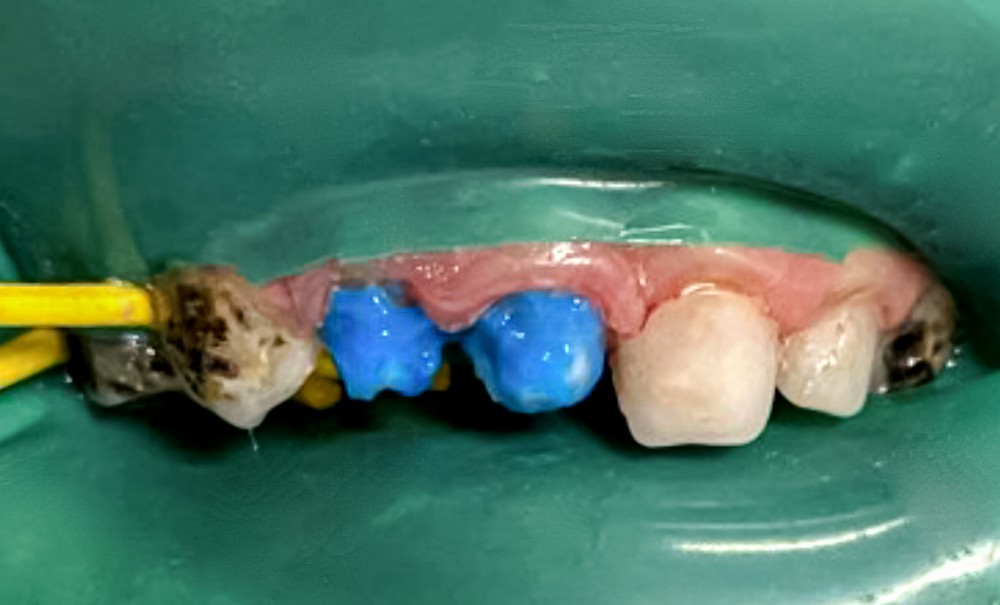

La carie précoce de l’enfance, ou CPE, provoque de multiples souffrances aussi bien physiques que psychologiques (honte et/ou moqueries) et peut avoir des répercussions sur la santé générale. L’émergence de nouveaux moyens de reconstitutions des dents temporaires ces dernières années a permis une amélioration de la gestion, notamment esthétique, de cette pathologie. Nous proposons ici de décrire une prise en charge de deux patients atteints de CPE à l’aide du coffret de coiffes « pediatric crown » d’Edelweiss.

Il existe plusieurs types de coiffes qui diffèrent par leurs compositions et leurs biocompatibilités. Dans cet article, nous nous concentrerons sur les coiffes en composite d’Edelweiss. L’objectif de leur utilisation est de restaurer l’esthétique et conserver la dimension verticale d’occlusion (DVO) après élimination des lésions carieuses et de prévenir l’apparition de foyers infectieux.

Ces couronnes en composite nano-hybride traitées au laser, vitrifiées et pré-polymérisées sont profilées pour imiter l’anatomie de toutes les dents temporaires et existent en différentes tailles. Elles se placent en méthode directe, en une seule séance, ce qui est particulièrement intéressant dans l’exercice de l’odontologie pédiatrique où la coopération est limitée.

Le tableau 2 présente le protocole de mise en place des coiffes selon les recommandations du fabricant.